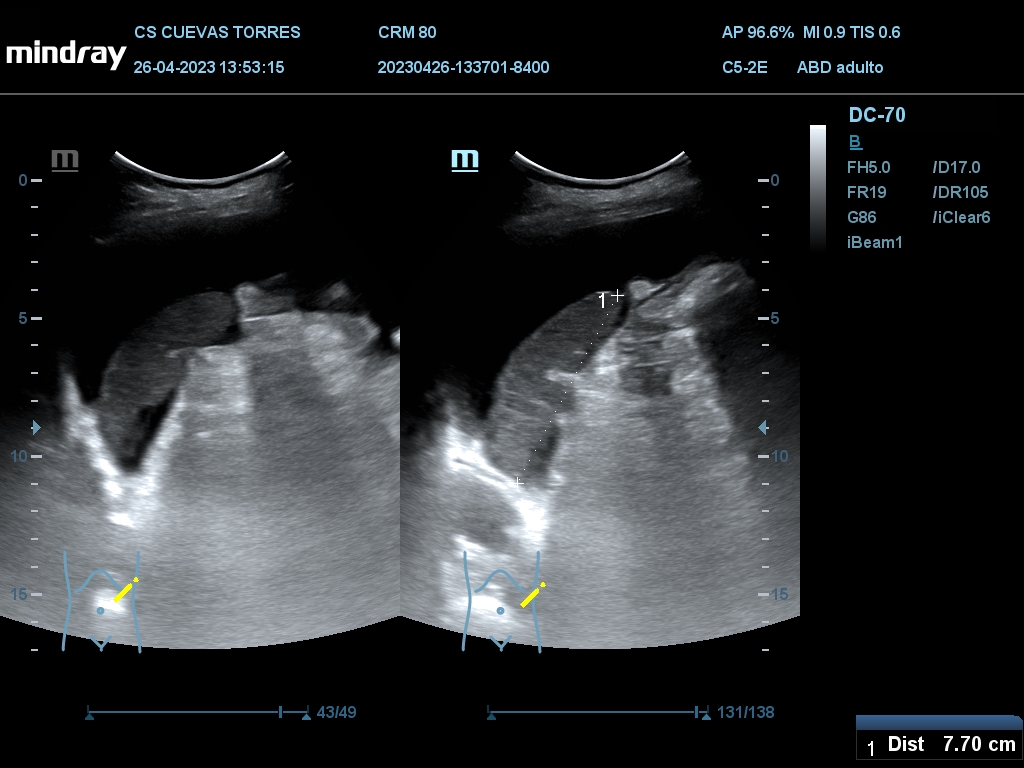

En la ecografía clínica observamos claramente la presencia de líquido libre desde el comienzo de la exploración. Continuando con el estudio Visualizamos circulación portal turbulenta y en el rastreo hepático una lesión ocupante de espacio (LOE) con captación Doppler de 7,45 cm de diámetro máximo.